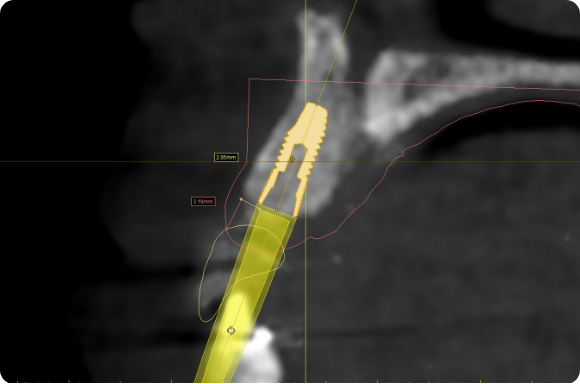

Utilising procedure-based education1, this level will help the clinician grow into more advanced surgical and prosthetic concepts with the treatment of single tooth anterior implant cases

Throughout this level, the cases will cover topics including: Evaluating buccal and apical bone for immediate placement, Grafting around immediate implants (Dual Zone Technique), Defining implant orientation – The Rules of Six, Assessing primary stability for immediate provisionalization, CAD/CAM abutment options and designs. At the completion of this level, participants will understand how to place and restore a single-tooth implant in the anterior zone. Participants are encouraged to continue their education in Level 4, which will focus on multi-unit cases.